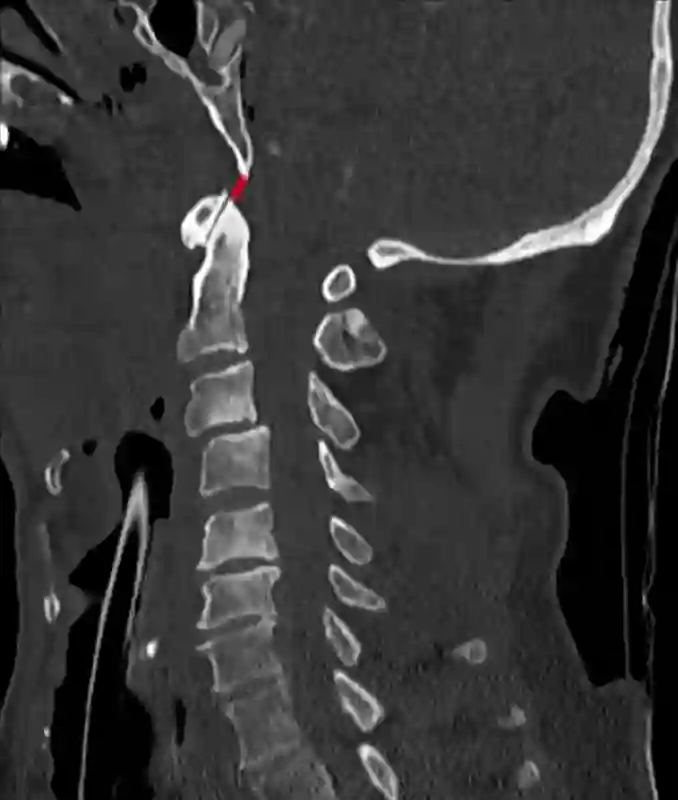

Das Basion-Dens Intervall (BDI) beschreibt die Distanz zwischen Basion und Dens.

Hierbei wird vom Basion die kürzeste Distanz zur Spitze des Dens gemessen.

Basion-Dens Intervall (BDI) im sagittalen CT der HWS (rote Linie).